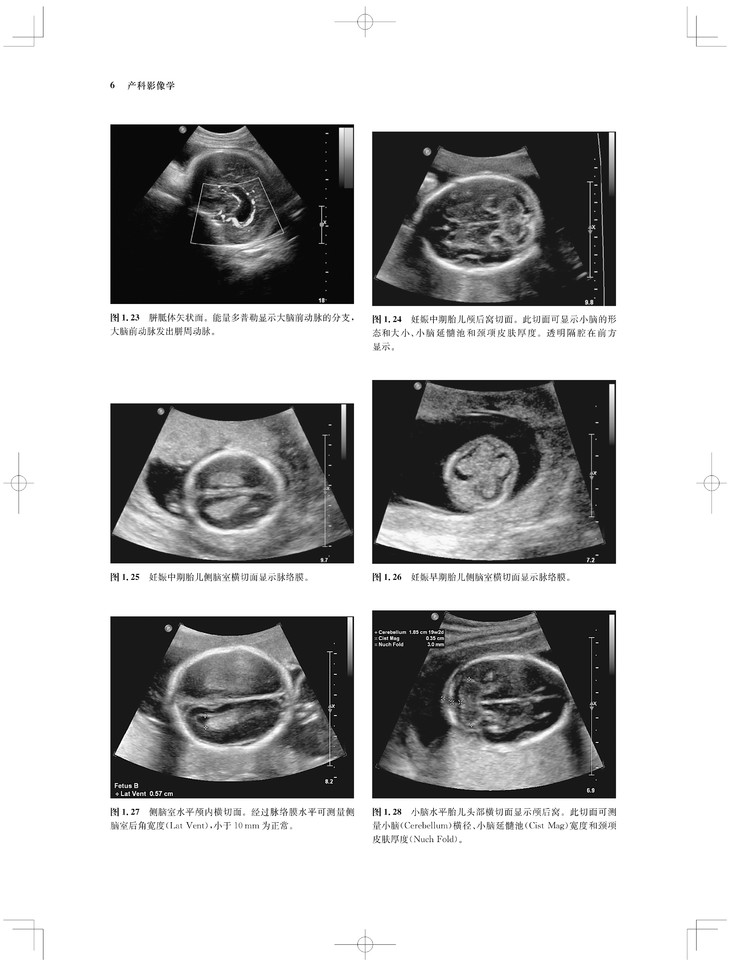

内容涵盖了胎儿宫内疾病的所有病种,从疾病的概述、流行病学、病因学、病理生理学,到临床表现、各类影像学技术的诊断和鉴别诊断,再到产前、产后的治疗和干预手段,都做了全面介绍,重点阐述了疾病的超声、X线、CT、MRI、PET、CT等影像学表现,以及诊断与鉴别诊断,并辅以大量标准化的影像学图片,图文并茂。

《产科影像学——胎儿诊断和监护》是Elsevier(Saunders)出版的“Expert Series”之一,由国际最顶尖的妇产科、生殖科、母胎医学和影像学专家共同编写,代表着该领域最顶尖的水平。书中配有大量典型影像图片,内容丰富全面,编写理念先进,侧重于疾病的影像学征象分析及鉴别诊断和诊断流程的制定,从临床思维上进行了更新;同时兼顾临床和病理医师,重点内容以列表、提要、要点的形式进行总结,提纲挈领,方便读者阅读、记忆。对于每天不断进行诊断与鉴别胎儿疾病的影像工作者、病理科和临床医师而言,具有重要的参考价值。